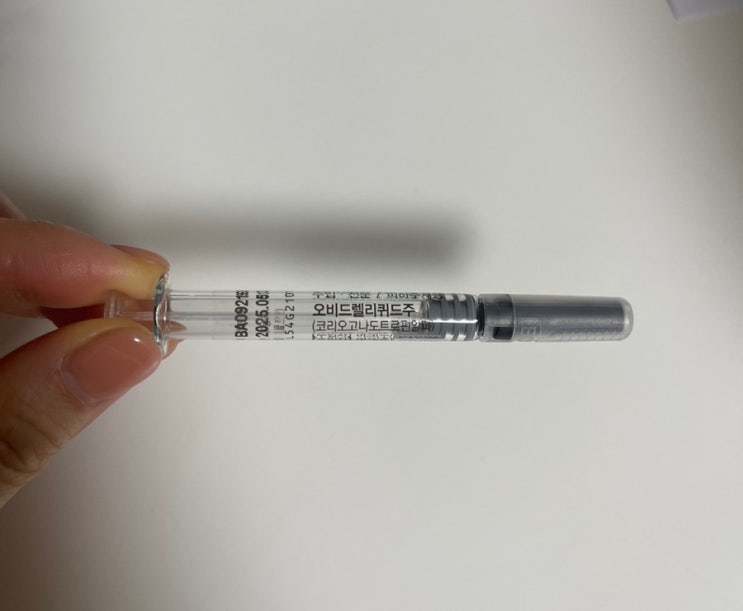

아기 심장소리도 듣고 했으니 카테고리를 임신일기로 변경해 보았다☺️ 내가 다녔던 난임병원 원장님께서...